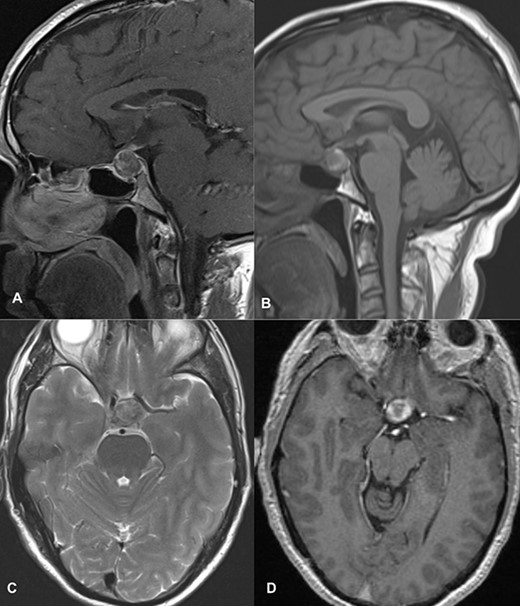

MRI imaging showed a 2 × 1.6 × 1.6 cm sized sellar lesion arising from the pituitary fossa with an intrinsic high T1 signal in the periphery, extending superiorly in the suprasellar region and laterally, causing a mass effect on the left cavernous sinus. A signal void was seen in T2-weighted images suggestive of hemorrhage (Fig. 3).

MRI images of post-contrast sagittal T1 (A), sagittal T1 (B), axial T2 (C), and post-contrast axial T1-weighted images (D) showing a 2 cm × 1.6 cm × 1.6 cm sized sellar lesion arising from the pituitary fossa extending superiorly in the suprasellar region and laterally causing a mass effect on the left cavernous sinus with intrinsic high T1 signal in the periphery and signal void on T2-weighted images suggestive of hemorrhage.